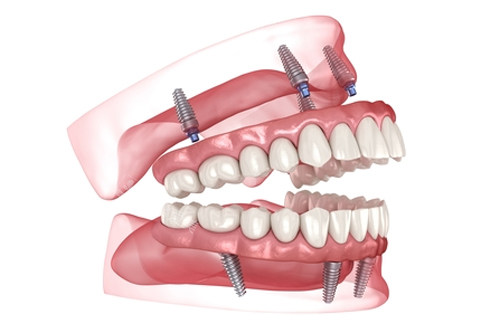

all-on-4全口种植牙模型图

all-on-6全口种植牙示意图